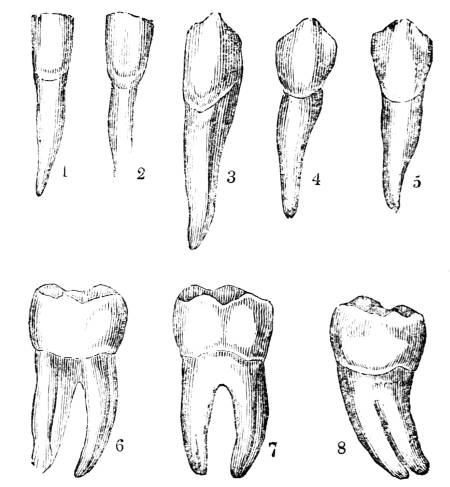

View of the trachea, showing, first, the division of the

tube into the right and left bronchus, and the subdivision

of the bronchi into the bronchial tubes; and secondly, the

membranous and cartilaginous tissues of which the organ

is composed.

required for this generation of carbonic acid is

acid, formed by the union of these elements,